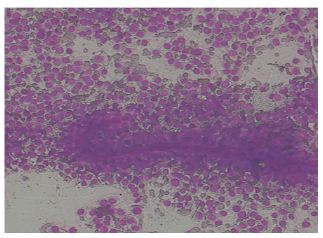

On ‘hook test’ (Figure 2) we could not hook finger around any anterior structures with elbow in flexed and supinated position. Pre operative quick DASH score was 57. X-ray showed no bony abnormality and an MRI confirmed complete rupture (Figure 3) and marked retraction of distal biceps tendon from bicipital tuberosity of the radius. Since the duration of injury was just one month we planned for reinsertion of tendon to bicipital tuberosity using fibre wire and an anchor screw. After pre anaesthesia evaluation patient was taken up for surgery. We went through anterior approach using a curved single incision over antecubital fossa without a tourniquet, and retrieved the tendon from the superior part of the incision (Figure 4).

Figure 4: Retrieval of the ruptured tendon from the proximal part of incision.